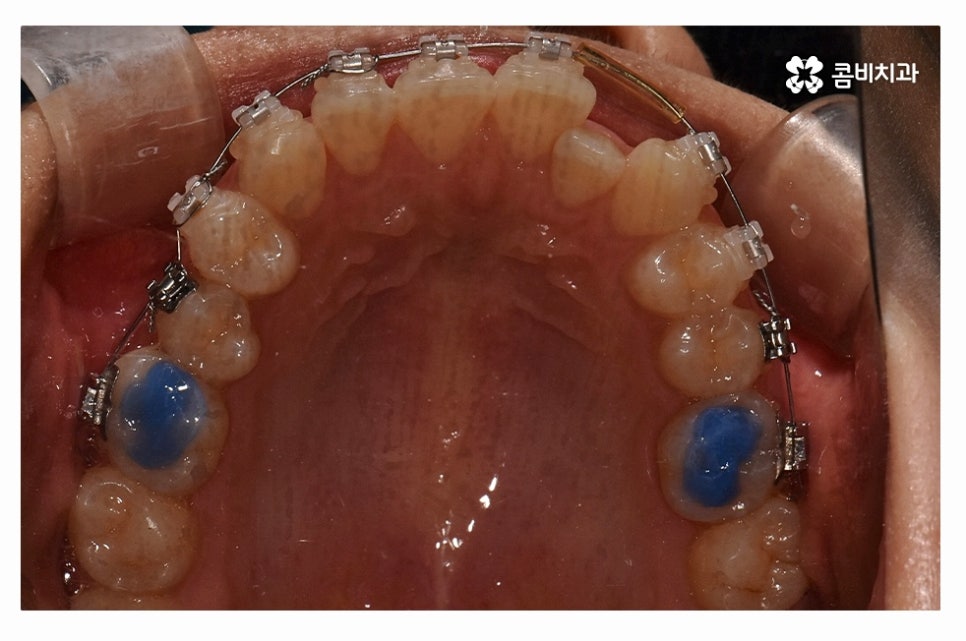

오늘 보여드릴 사례도 덧니교정이 비발치로 진행이 된 사례이며

치아의 이동 공간과 치아 상태, 골격, 얼굴형 등을

종합적으로 판단할 때 비발치로도 진행이 가능했던 사례라고 할 수 있어요.

위 환자분의 사례처럼 클리피씨교정이 보편적으로 많이 활용되고 있는데요.

클리피씨교정은 치아의 이동이 일반 장치에 비해 상대적으로

빠르기 때문에 치료 기간이 단축될 수 있으며

통증의 감소, 내원 횟수를 줄일 수 있다는 장점 등이 있어요.